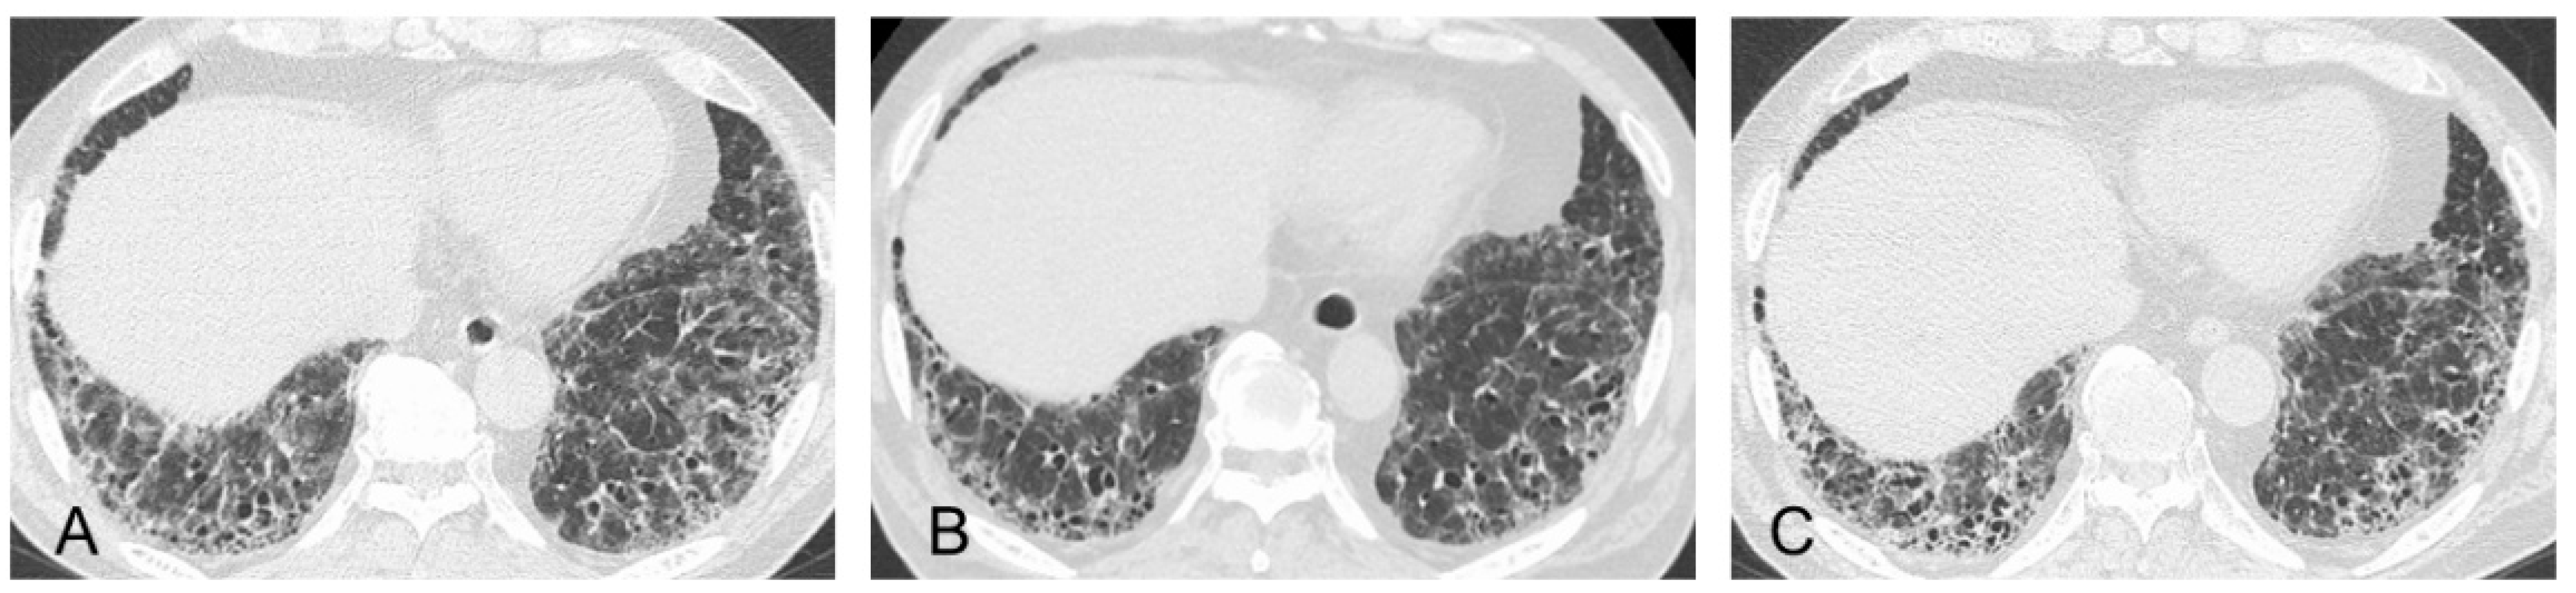

| HRCT findings | Framework: Subpleural and basal predominant distribution is often heterogeneous | |

| Increased attenuation around honeycombing and traction bronchiectasis (19–39%) | ― | |

| Pathological findings | Framework: Dense fibrosis with architectural distortion, predominant subpleural and/or paraseptal distribution of fibrosis | |

| More prominent inflammatory cell infiltration and cellular bronchiolitis compared with IPF | ― | |